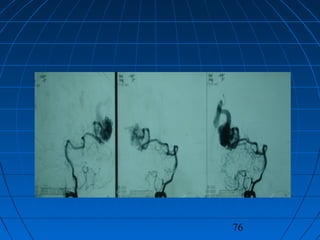

 İ.A.: 27 yaşında erkek hastaİ.A.: 27 yaşında erkek hasta

 BaşağrısıBaşağrısı

75

76

CERRAHİCERRAHİ

 Sol oksipital kranyotomiSol oksipital kranyotomi

 AVM’nin total rezeksiyonuAVM’nin total rezeksiyonu

 PostoperatifPostoperatif

Nörolojik Muayene ve DSA:Nörolojik Muayene ve DSA:

NormalNormal